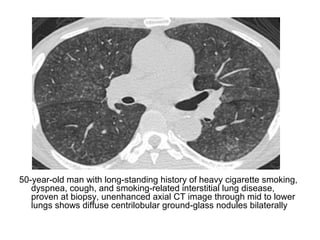

50-year-old man with long-standing history of heavy cigarette smoking,

dyspnea, cough, and smoking-related interstitial lung disease,

proven at biopsy, unenhanced axial CT image through mid to lower

lungs shows diffuse centrilobular ground-glass nodules bilaterally